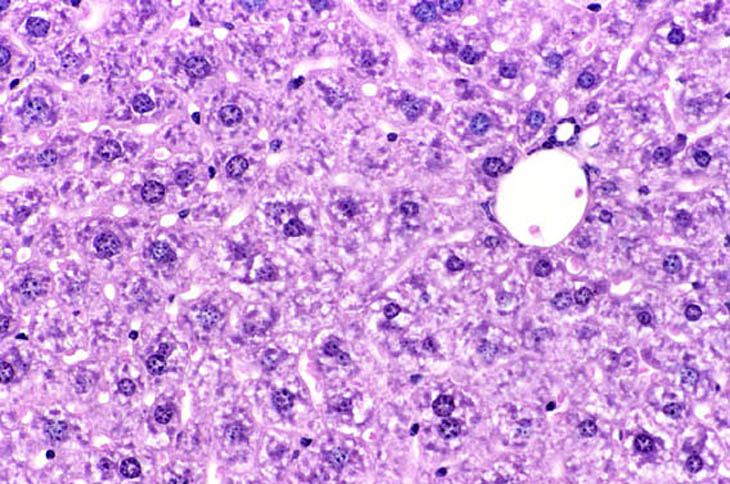

Immersion fixation in non-fasted mouse liver. Fixative was 10% NBF.